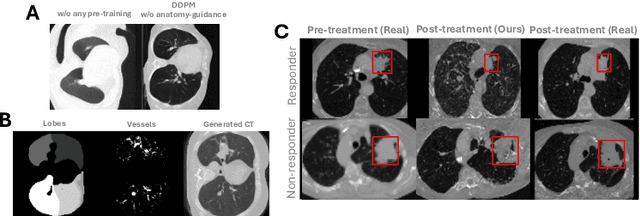

Abstract:Accurately predicting immunotherapy response in Non-Small Cell Lung Cancer (NSCLC) remains a critical unmet need. Existing radiomics and deep learning-based predictive models rely primarily on pre-treatment imaging to predict categorical response outcomes, limiting their ability to capture the complex morphological and textural transformations induced by immunotherapy. This study introduces ImmunoDiff, an anatomy-aware diffusion model designed to synthesize post-treatment CT scans from baseline imaging while incorporating clinically relevant constraints. The proposed framework integrates anatomical priors, specifically lobar and vascular structures, to enhance fidelity in CT synthesis. Additionally, we introduce a novel cbi-Adapter, a conditioning module that ensures pairwise-consistent multimodal integration of imaging and clinical data embeddings, to refine the generative process. Additionally, a clinical variable conditioning mechanism is introduced, leveraging demographic data, blood-based biomarkers, and PD-L1 expression to refine the generative process. Evaluations on an in-house NSCLC cohort treated with immune checkpoint inhibitors demonstrate a 21.24% improvement in balanced accuracy for response prediction and a 0.03 increase in c-index for survival prediction. Code will be released soon.